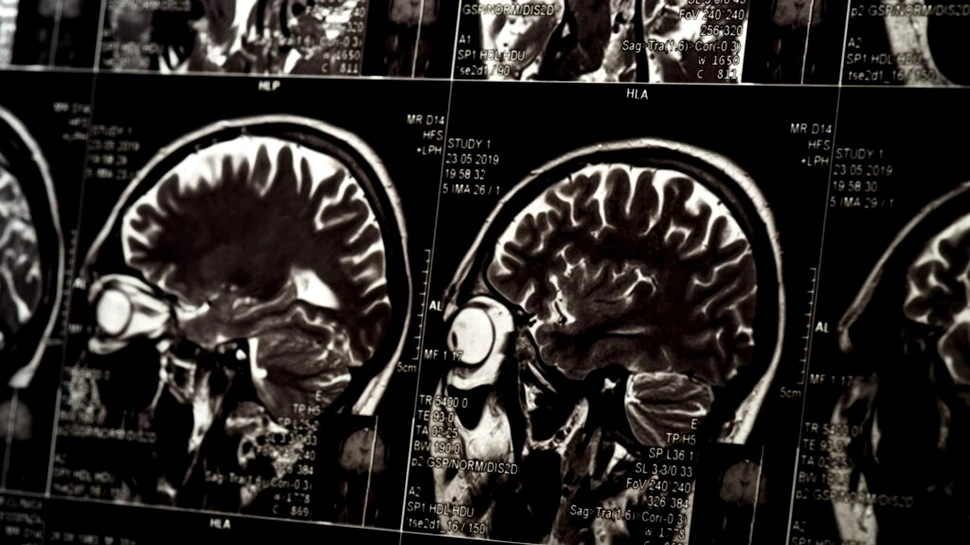

O echipă de neurologi și neurochirurgi de la UCL (Anglia) a identificat părțile creierului implicate în amintirea cuvintelor și modul în care acestea sunt afectate de o formă comună de epilepsie.

Un nou studiu, publicat în revista Brain Communications, a arătat că micșorarea anumitor zone din partea frontală și laterală a creierului (cortexurile prefrontal, temporal și cingular, precum și hipocampul) este asociată cu dificultăți în reținerea cuvintelor.

Această descoperire evidențiază faptul că rețeaua responsabilă de formarea și stocarea amintirilor legate de cuvinte este dispersată în întregul creier.

„Capacitatea de a memora și de a-ți reaminti cuvinte este esențială pentru buna funcționare a memoriei zilnice. Tomografiile cerebrale detaliate prin RMN sunt utilizate pentru a identifica cauzele epilepsiei și pot indica dacă anumite părți ale creierului au suferit micșorări. Prin măsurarea acestor modificări și corelarea lor cu performanțele în reținerea cuvintelor, putem determina părțile creierului implicate în amintirea cuvintelor. În plus, dacă medicamentele nu reușesc să controleze crizele epileptice, aceste descoperiri ne ajută să ghidăm intervențiile chirurgicale astfel încât să evităm afectarea regiunilor esențiale pentru memorie”, a explicat profesorul John Duncan, autorul principal al studiului.

Pentru a măsura dimensiunea și forma diverselor regiuni ale creierului, cercetătorii au utilizat scanări RMN de înaltă rezoluție. Acestea au vizat atât cortexul cerebral (stratul exterior al creierului, responsabil pentru gândire, memorie, atenție, percepție, conștientizare și limbaj), cât și zone specifice din hipocamp (structura implicată în învățare, memorie și orientare spațială).